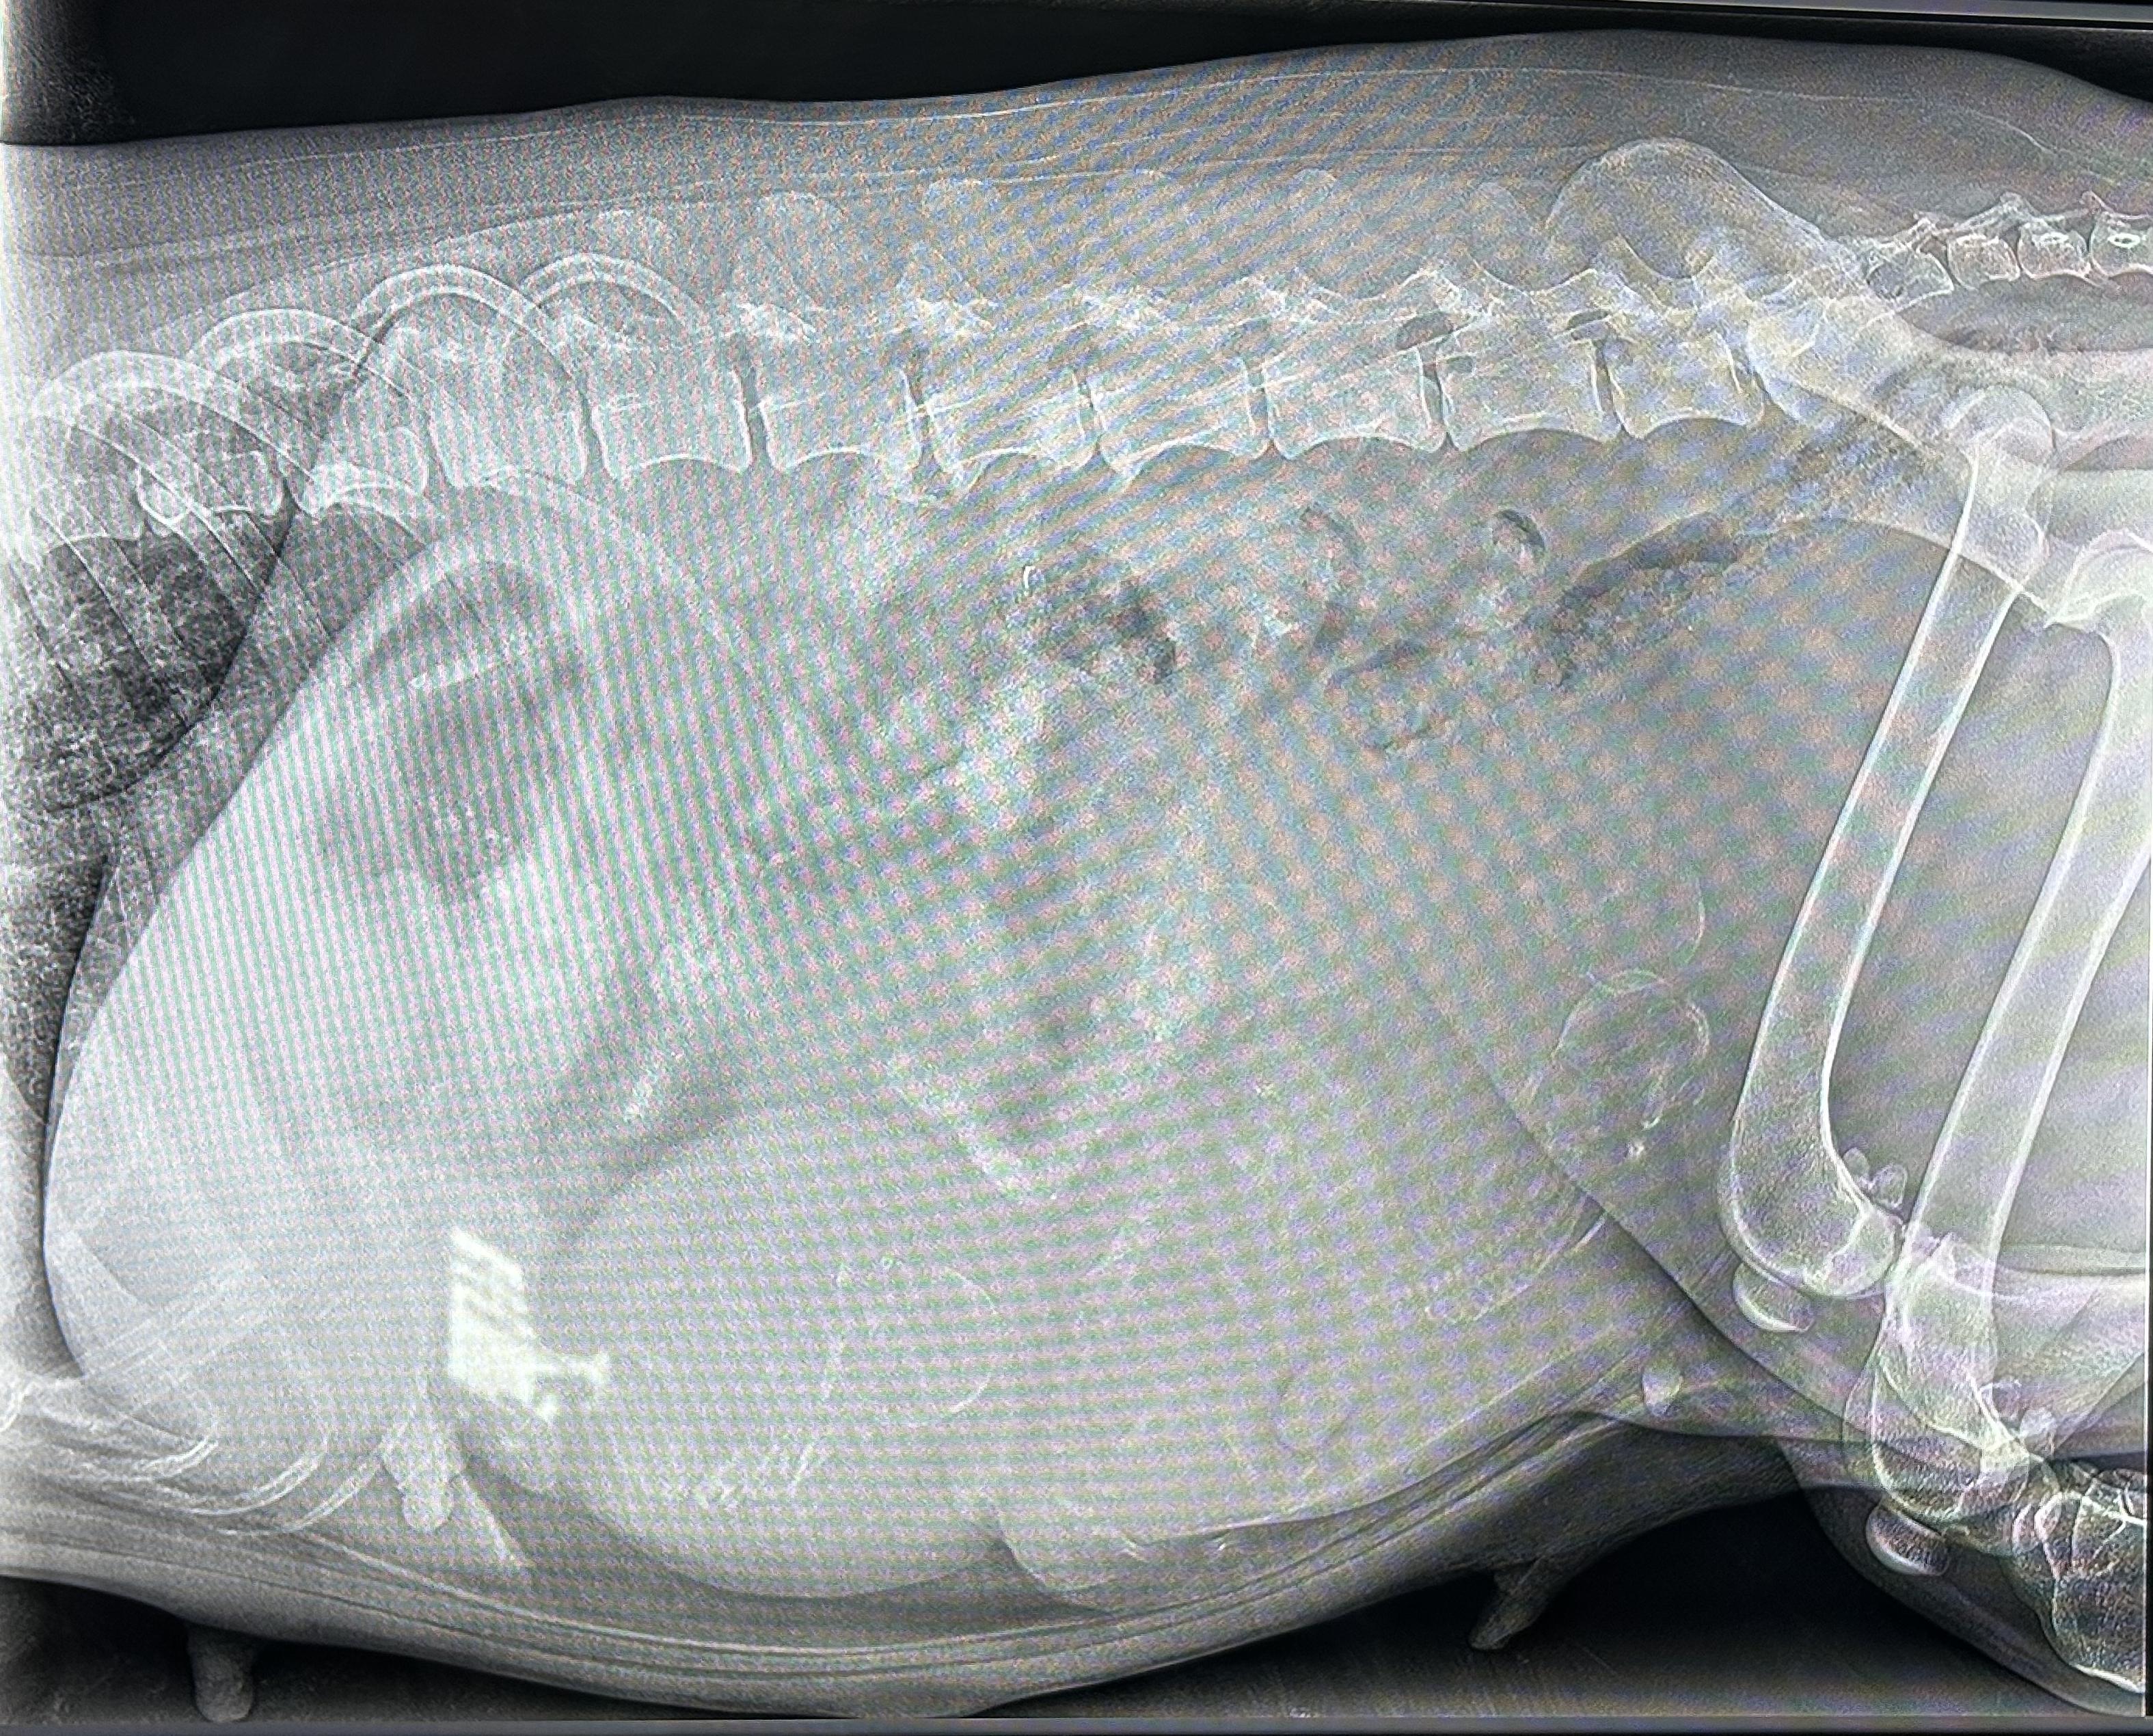

Jettes Welpen 2026

| Ultraschall | Roentgen | Geburt | 1. Woche | 2. Woche | 3. Woche | 4. Woche | 5. Woche | 6. Woche | 7. Woche | 8. Woche | 9. Woche | 10. Woche | 11. Woche | 12. Woche | 14. Woche |